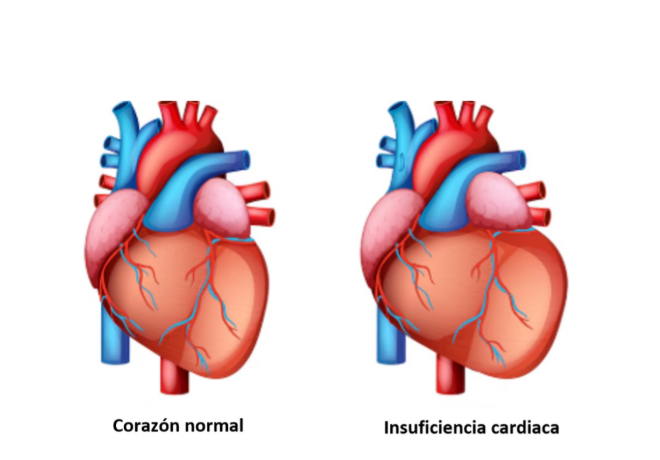

ISUFICIENCIA CARDÍACA. La insuficiencia cardíaca (IC) es un síndrome clínico en el que el corazón no puede bombear la sangre necesaria para cubrir las demandas del organismo, o solo lo logra a expensas de presiones de llenado elevadas. CLASIFICACIÓN PRINCIPAL Según...